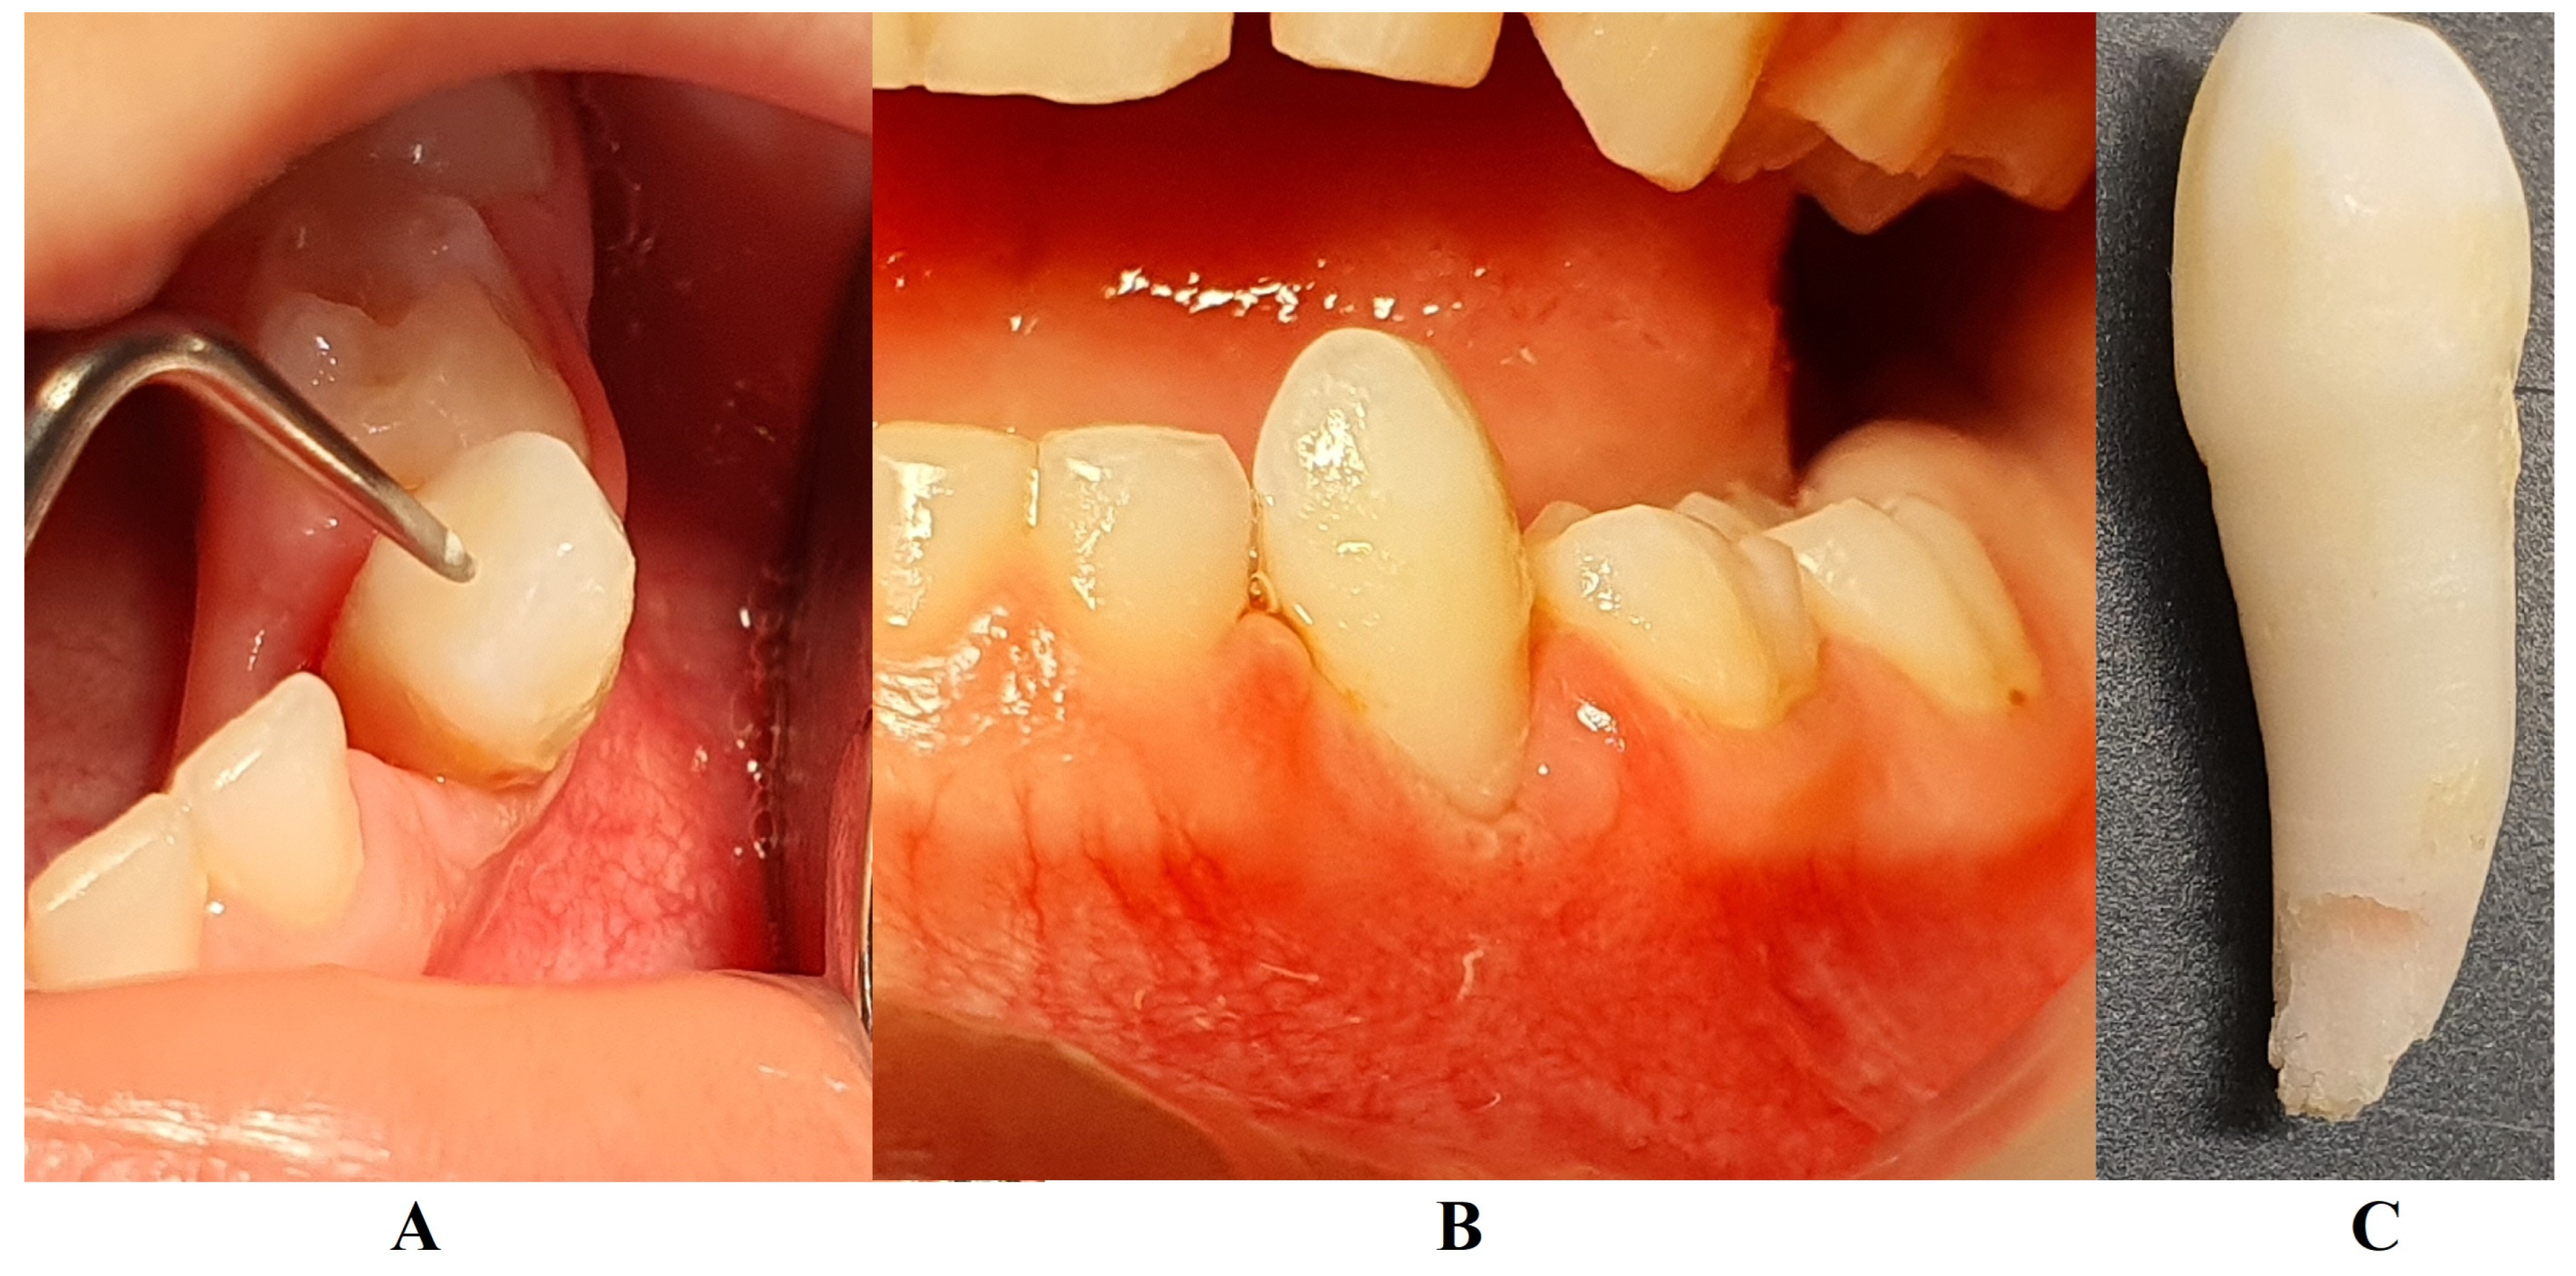

In August 2023, the family consulted another clinician abroad (2 August 2023, Klausenburg/Cluj-Napoca—Romania) since the parent’s concerns related to the deteriorating local conditions (inflamed periodontium around lower deciduous canine and enhanced movement, Figure 2). The parents presented the entire documentation gathered from previous examinations including paraclinical test results and X-rays [1]. After reviewing the familial history and clinical and paraclinical examinations (3rd of August), the initial hypophosphatasia/hyperphosphatasia suspicions were dismissed (also confirmed by late September 2023 through negative genetic test results), and the Stage IV grade C localized periodontitis/pre-puberal localized aggressive periodontitis-LPP diagnosis was made. No orthodontic problems were detected during the clinical examination (also confirmed by previous clinical exams), and only the hyper-eruption of the deciduous left canine due to advanced periodontal loss and surrounding inflammation (Figure 2) was noted [1]. When setting up the LPP diagnosis, the previous X-rays (Figure 1) were taken into consideration along with the young patient’s other paraclinical results. For laboratory confirmation, a periodontopathic bacteria sample was taken (3rd of August). Due to the advanced localized periodontal loss and tooth movement, only professional hygiene and adjuvant topical applications with amoxicillin and metronidazole association around the inflamed periodontal pocket for a period of 10 days were prescribed. The parents were informed about all these above-mentioned issues, and the most likely loss of the tooth but also the necessity of instituting a general antibiotic treatment and follow-up of the case. The family left Klausenburg (Romania) 5 August 2023. The periodontopathic bacteria test was highly positive on 16 August 2023 with Fusobacterium nucleatum/periodonticum and Capnocytophaga. The tooth was finally lost in early September (Figure 2) [1].

The unusualness of this case is due to several aspects. The first is related to the extremely young age of the patient (i.e., 4 years old in February 2023, deciduous dentition), with an insidious onset, and apparently no familial aggregation or history. The second aspect is related to the misdiagnosis of metabolic diseases (i.e., hypophosphatasia/hyperphosphatasia as written) with oral manifestations (since no therapeutic measures were taken) despite the initial radiographical (i.e., Figure 1) and clinical examination that suggested a clear picture of an unusual LPP (e.g., the lower left canine involvement). The third aspect is related to the lack of therapeutic measures that rapidly set the course for the periodontal and 7.3 loss, in an interval of around 7 months (Figure 2) and the further progression involving other oral sites (Figure 3 and Figure 4). The fourth aspect is related to the evolution under adequate treatment (despite no written report to guide it) and the periodontal gain over a period of around 8 months following the antibiotic therapy (Figure 5 and Figure 6).

Figure 2. Images of the lower left canine: (A) and (B)—advanced mobility and hyper-eruption due to advanced periodontal loss and inflammation (2 August 2023), (C)—7.3, lost in September 2023.